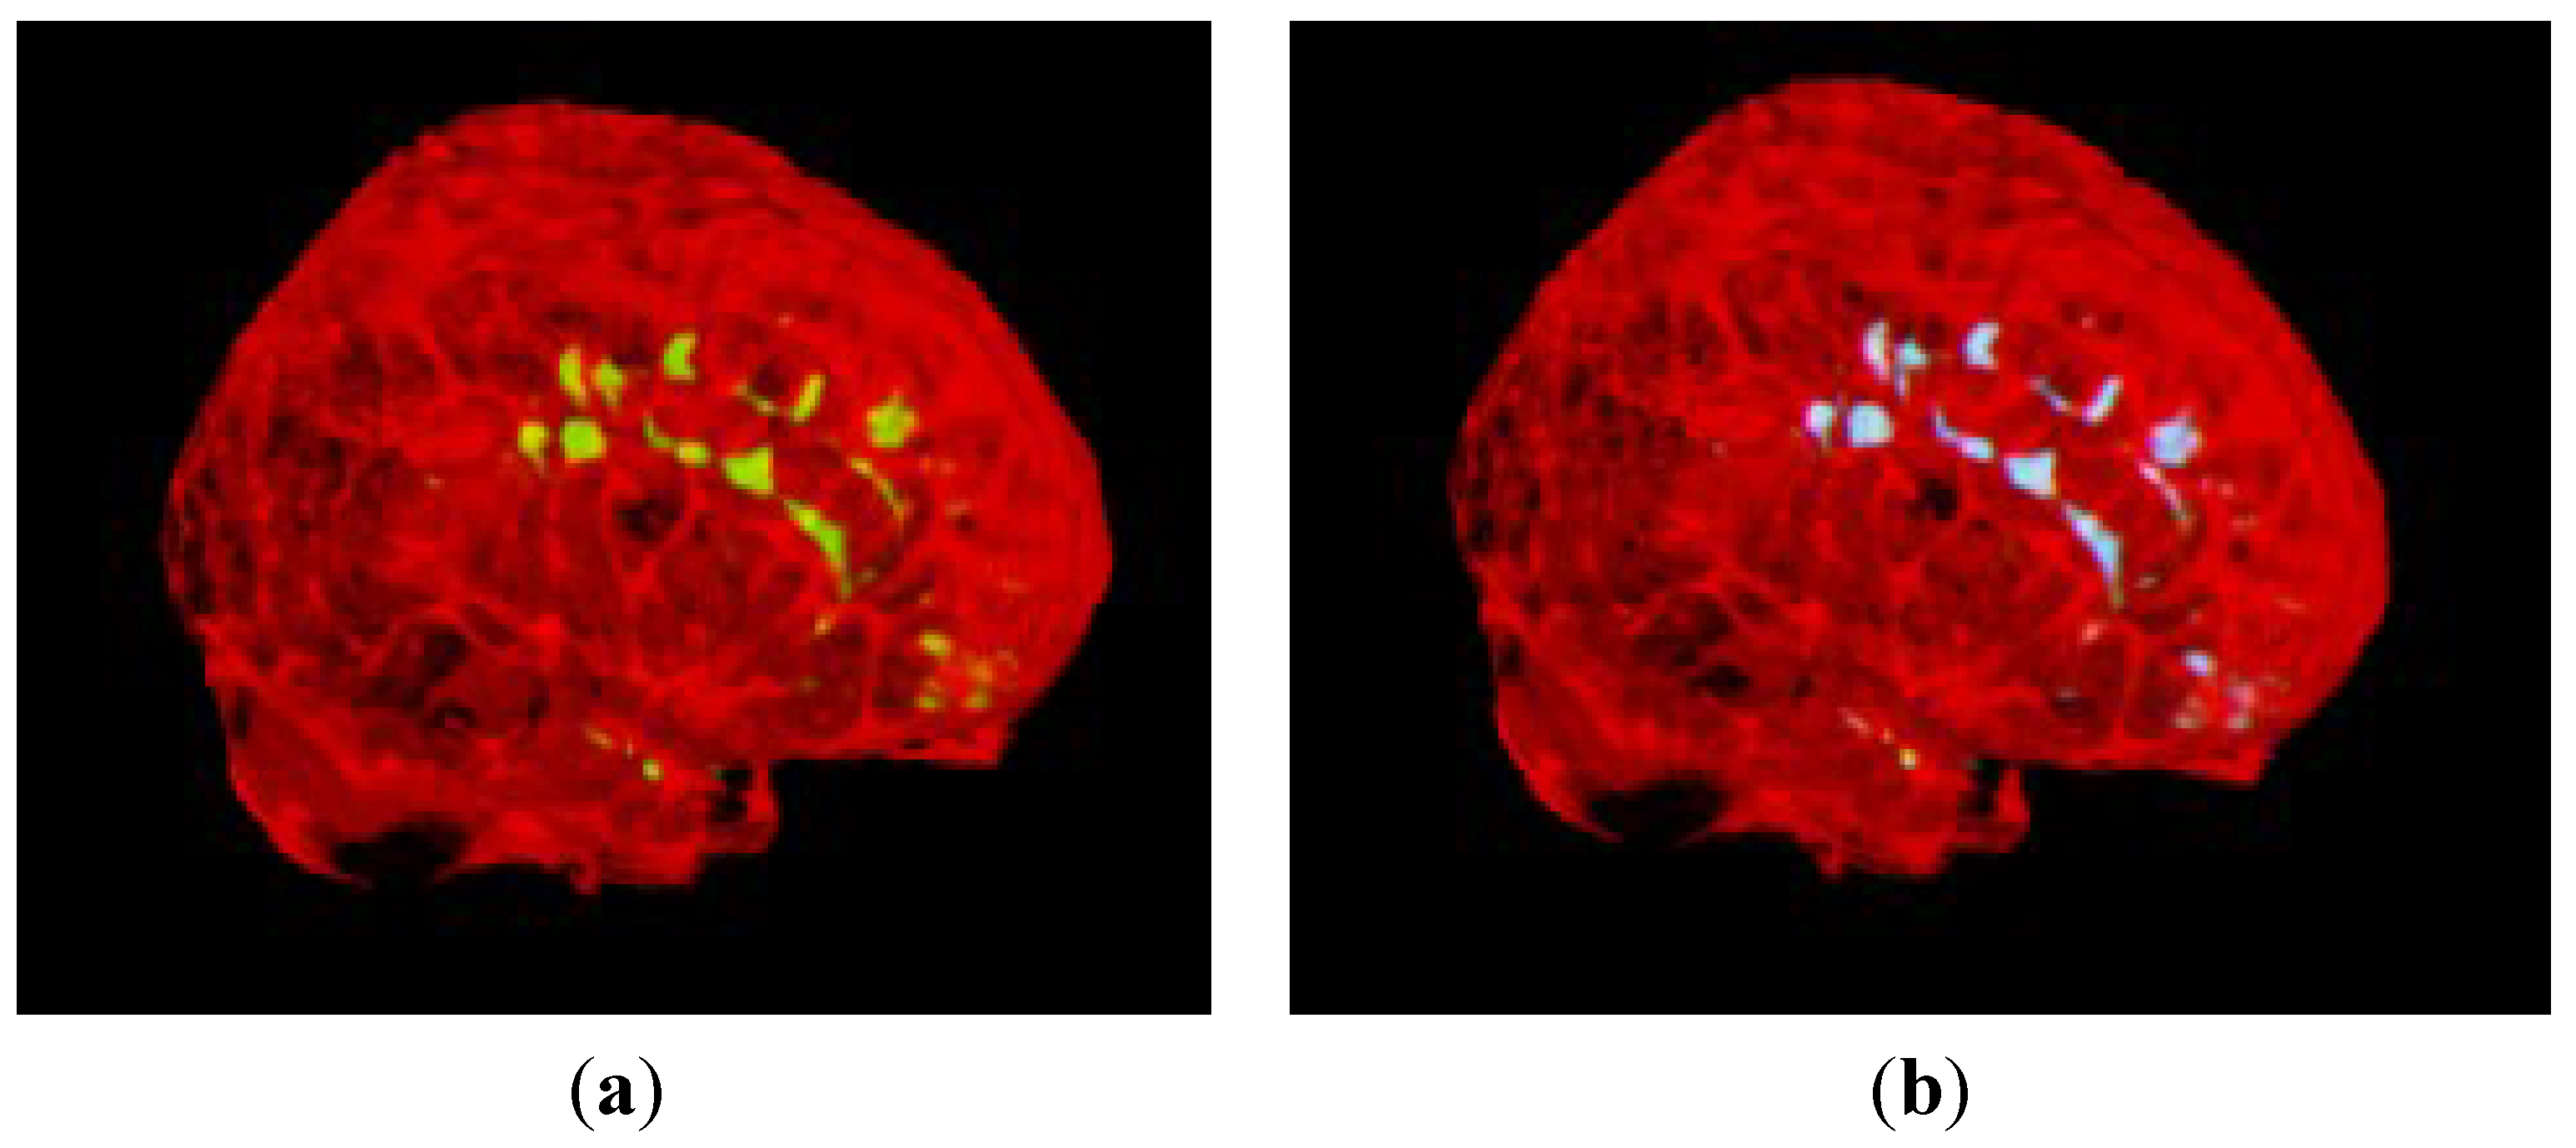

3.2. Segmentation of MS Lesions in a Whole Brain Volume

3.2.2. Brain Data with Moderate MS Lesions

3.2.3. Brain Data with Severe MS Lesions